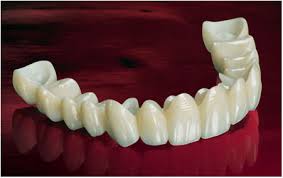

Bridge

Zirconia Crown

Bridge

A dental bridge is a prosthetic device used to replace one or more missing teeth. It consists of two or more crowns placed on the natural teeth (called abutment teeth) adjacent to the gap, with a false tooth or teeth (called pontics) in between. A dental bridge consists of two or more crowns for the teeth on either side of the gap (known as abutment teeth) and a false tooth (called a pontic) in between.

Zirconia crown and bridge

A dental zirconia crown and bridge is a type of prosthetic restoration designed to replace missing teeth or cover damaged ones, utilizing high-quality zirconia material. Zirconia is a durable, biocompatible ceramic that offers excellent aesthetics, mimicking the natural appearance of teeth. The crown is placed over a tooth to restore its shape, size, and function, while a bridge spans the gap created by one or more missing teeth, anchoring to adjacent healthy teeth for stability. These restorations are known for their strength, resistance to wear, and minimal risk of allergic reactions, making them suitable for patients with metal sensitivities. Additionally, zirconia crowns and bridges are highly stain-resistant and can last for many years with proper oral hygiene.